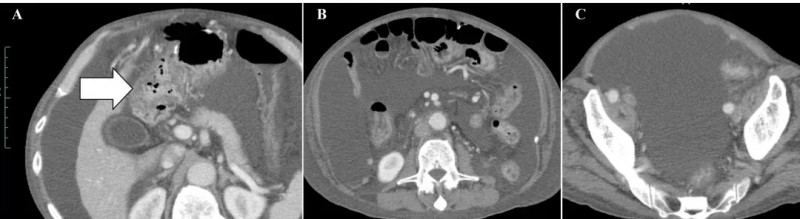

该患者为一位72岁男性,确诊为IV期原发性十二指肠腺癌(T3N2M1),伴远端淋巴结转移。他先接受胃空肠旁路手术,术后行S-1(口服嘧啶氟化物衍生药物)+奥沙利铂化疗,肿瘤虽有缩小但后续出现腹膜播散。二线伊立替康化疗启动后第二个月,腹膜播散、恶性腹水及恶病质迅速恶化,腹部CT显示大量恶性腹水及十二指肠周围大网膜脏脂肪征,化疗失败且无合适后续治疗方案,患者最终入组,并于2020年1月正式开始接受WT1/MUC1-DC(WT1和MUC1肽脉冲树突状细胞)+CAT疗法治疗。

治疗效果十分显著:治疗前腹部CT可见十二指肠周围明显扩张的大网膜(详见下图A箭头所示)、大量恶性腹水(详见下图B、C)。

▲图源“Cureus”,版权归原作者所有,如无意中侵犯了知识产权,请联系我们删除